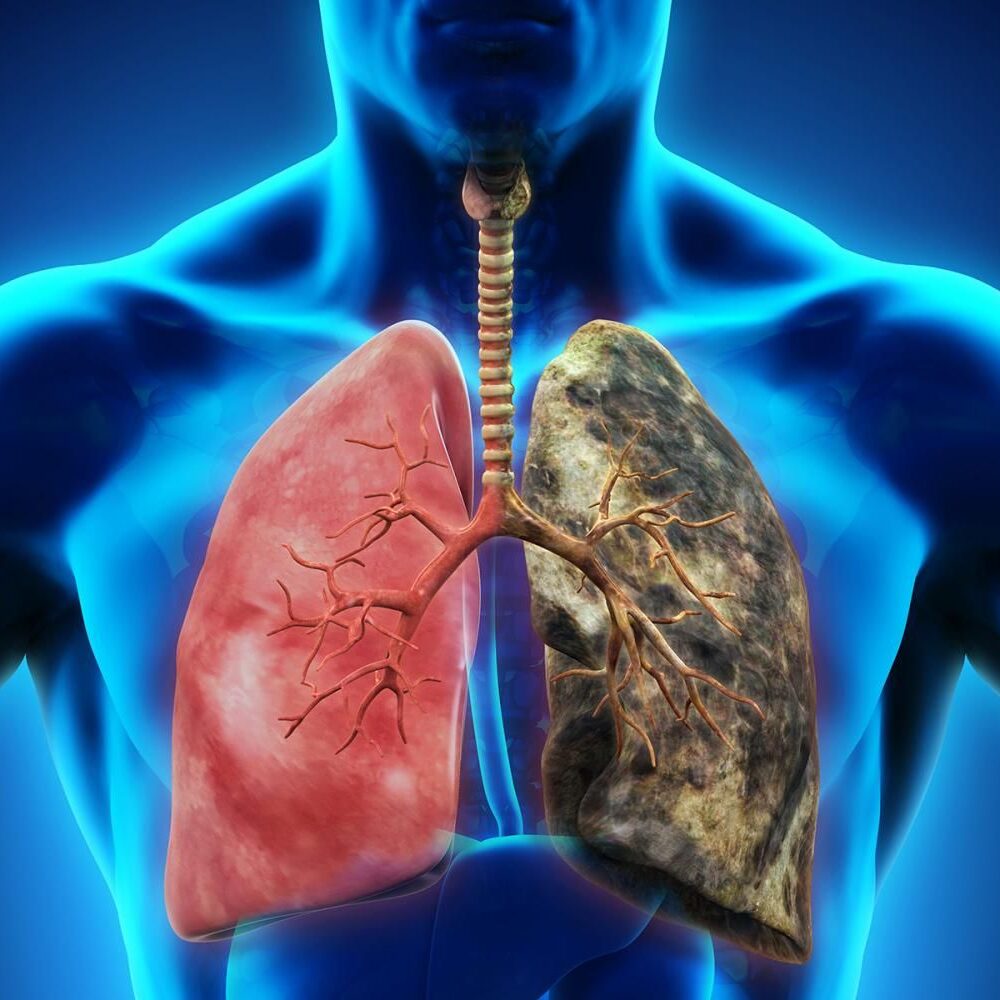

Civilizační choroby

Nadváha a obezita výrazně zvyšují riziko vzniku civilizačních chorob, jako jsou: Cukrovka 2. typu, Vysoký krevní tlak, Onemocnění srdce a cév (infarkt, mrtvice), Některé typy rakoviny. Zhubnutím se tyto rizikové faktory snižují, organismus se méně zatěžuje a lépe funguje. Snížení rizika chronických onemocnění